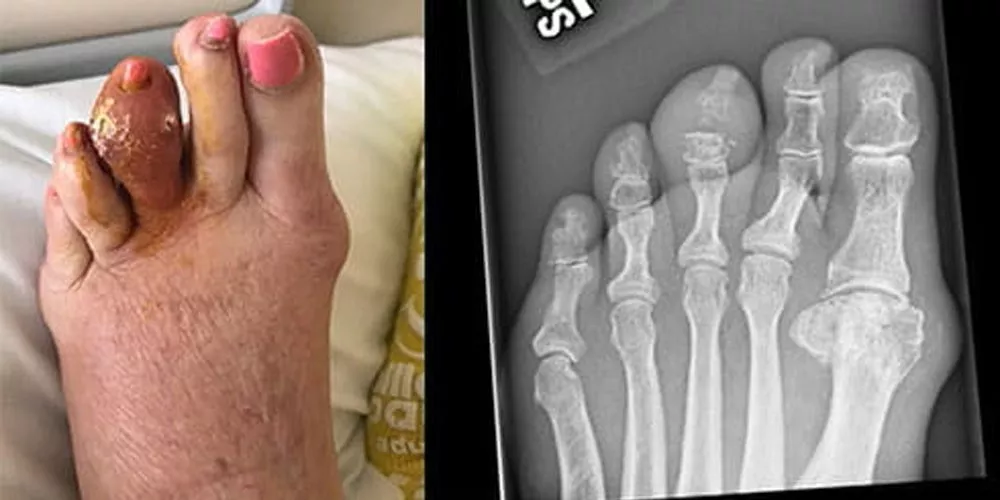

Рис 3. “Классический” дебют подагры: поражение первого плюсне-фалангового сустава, сопровождающееся острой болью, покраснением и отеком [9].

Рис 6. Подагра с поражением среднего пальца левой стопы. На этой фотографии виден большой тофус на среднем пальце левой стопы, который вскрылся с высвобождением затвердевших масс мочевой кислоты. На рентгеновском снимке видна эрозия средней фаланги и дистального межфалангового сустава [9].